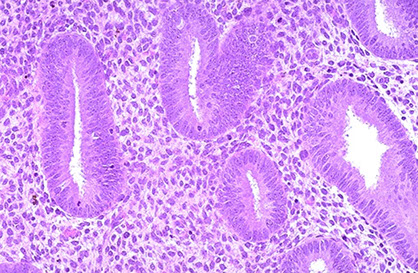

Endometrium has simple columnar epithelial lining c assoc simple tubular endometrial glands and endometrial stroma (the lamina propria)

- made of 2 layers: functional layer (affected by hormones and blood supply) and a basal layer (not affected, has pretty constant look of weakly prolif glands and cellular spindled stroma)

Menstrual cycle divided into proliferative and secretory phases

Proliferative phase

Much more variable than secretory phase, regeneration of endometrium that has sloughed off from last menses

- endometrial glands lined by pseudostratified columnar c dense chromatin and small nucleoli

- early in this phase (d4-7) the surface endometrium is thin and orderly

- in mid-phase (d8-10) the glands are a little more zigzag and surface is taller columnar, mits in stroma and epithelium

- late-phase - glands c wavy surface and more coiled glands, more abundant mits in epithelium and stroma, no more stromal edema

proliferative endometrium